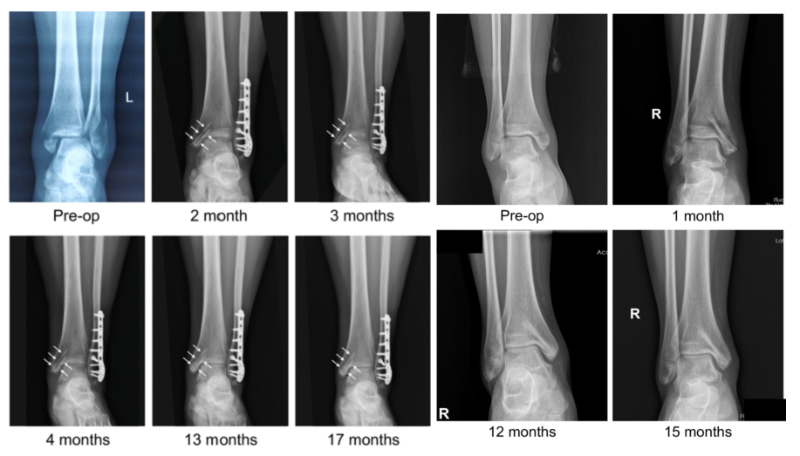

近日,國際骨科臨床轉(zhuǎn)化期刊《Journal of Orthopaedic Translation》在線發(fā)表了由上海交大戴尅戎院士、郝永強(qiáng)教授團(tuán)隊(duì)和丁文江院士、袁廣銀教授團(tuán)隊(duì)合作發(fā)表的可降解鎂合金骨釘1-2年的臨床試驗(yàn)觀察結(jié)果,所有患者術(shù)后內(nèi)踝骨折愈合,功能恢復(fù)。研究證實(shí)了可降解鎂合金螺釘治療內(nèi)踝骨折的臨床療效及其生物安全性,為全降解鎂合金植入物等高端醫(yī)療器械進(jìn)一步的臨床推廣應(yīng)用奠定了堅(jiān)實(shí)基礎(chǔ),相關(guān)成果以“Effectiveness and safety of biodegradable Mg-Nd-Zn-Zr alloy screws for the treatment of medial malleolar fractures”為題在線發(fā)表于Journal of Orthopaedic Translation,27 (2021) 96–100。這是國內(nèi)首個可降解醫(yī)用鎂合金臨床試驗(yàn)的公開報道,也是國際首款含有功能涂層的可降解鎂合金骨釘?shù)呐R床試驗(yàn)結(jié)果的公開報道,具有里程碑意義。

醫(yī)用鎂合金骨內(nèi)植物臨床試驗(yàn)研究突破性進(jìn)展(圖1)